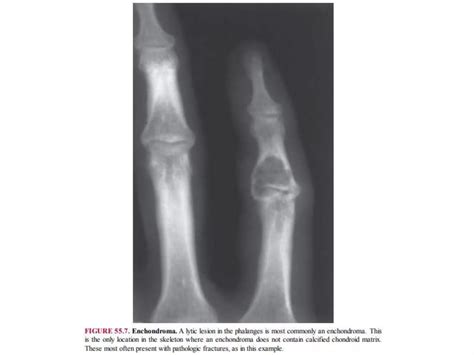

At its core, a lytic lesion is a focal area within the bone structure where mineral density has been significantly reduced. This reduction creates "holes" or voids in the bone, which are easily identified on X-rays as darker, radiolucent patches. The process is usually driven by the activation of osteoclasts—the cells responsible for breaking down bone tissue. When pathological processes, such as the invasion of metastatic cancer cells or inflammatory cytokines, trigger these cells, they erode the bone matrix prematurely.

The differential diagnosis for these lesions is vast, but clinicians often categorize them based on age, location, and the specific "look" of the lesion:

Effective management of Lytic Skeletal Lesions relies on a systematic imaging protocol. A plain radiograph is almost always the initial step. If the lesion has a sclerotic rim, it may suggest a slow-growing, benign process. Conversely, an ill-defined or "moth-eaten" appearance usually mandates immediate follow-up with more sophisticated imaging like an MRI to assess the extent of the marrow infiltration and soft tissue involvement.